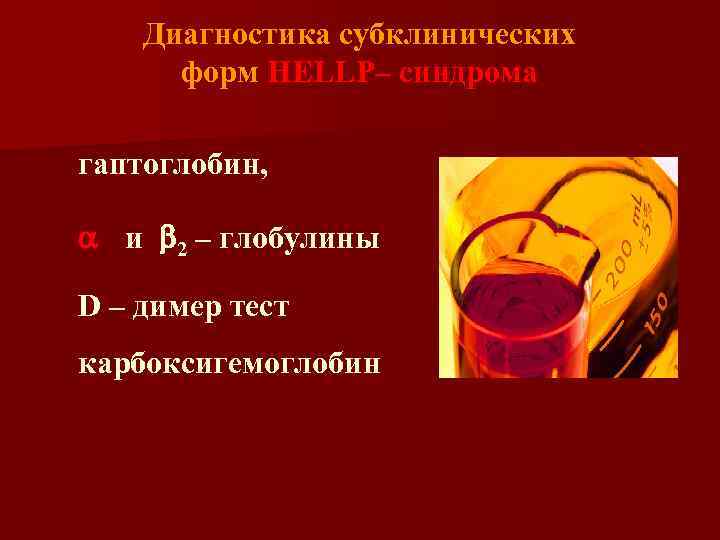

Диагностика субклинических форм HELLP– синдрома гаптоглобин, a 2 и b 2 – глобулины, D – димер тест, карбоксигемоглобин.

Диагностика субклинических форм HELLP– синдрома гаптоглобин, a 2 и b 2 – глобулины, D – димер тест, карбоксигемоглобин.